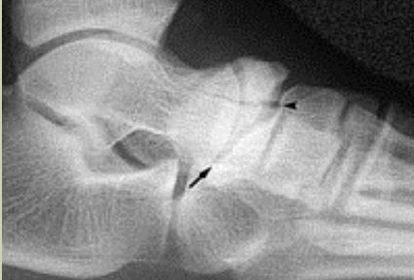

What is this? What is shown by A and B? | STJ coalition A = talar neck spurring B = Halo or 'C' sign |